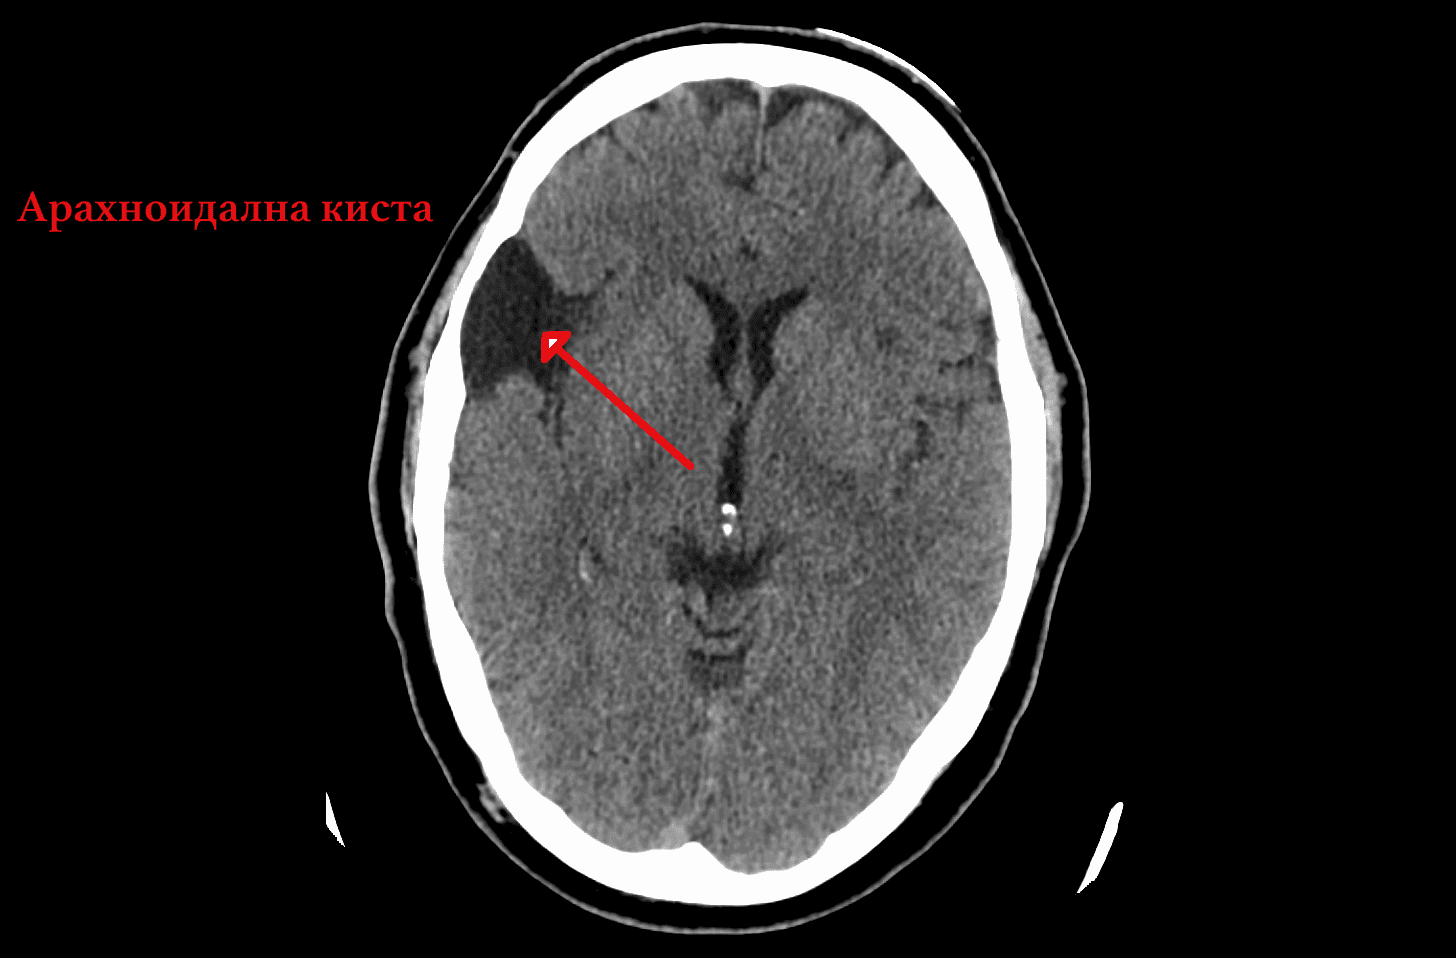

- Арахноидални кисти

Правилното разграничаване има голямо значение, тъй като прогнозата и управлението на различните аномалии значително се различават.